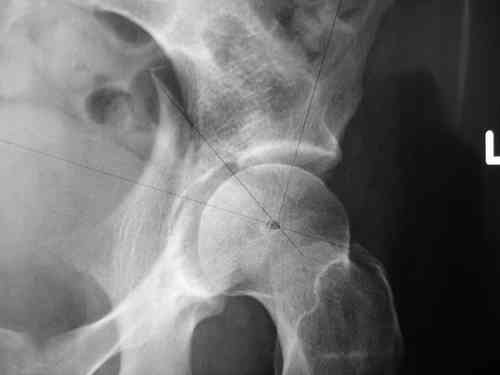

Dear group,30 years age female MVA front seat, head trauma + post column left acetabular fracture, 2.5 weeks skeletal traction. She is now conscious but still confused without any surgical treatment for brain edema.

Latest X rays and CAT is attached.Fracture within first 1.5 cm from the weight bearing dome, although AP and Obtrator oblique good, iliac oblique view reveals some displacement.I'm not sure that nonsurgical treatment will be OKHüseyin DemirorsBaskent UniversityDept of Orthopedics and TravmatologyAnkara TURKEY

My vote, given the amount of displacement on the iliac oblique and CT scan, would be for ORIF thru a posterior approach ASAP - these get pretty tough

I may get beat up for this, but I see very little displacement that concerns me on the CT. The radiograph is more concerning. I suspect it could look better, and the gap made smaller on CT. Not sure if it will affect outcome. I might give it a shot and try to see what could be done.